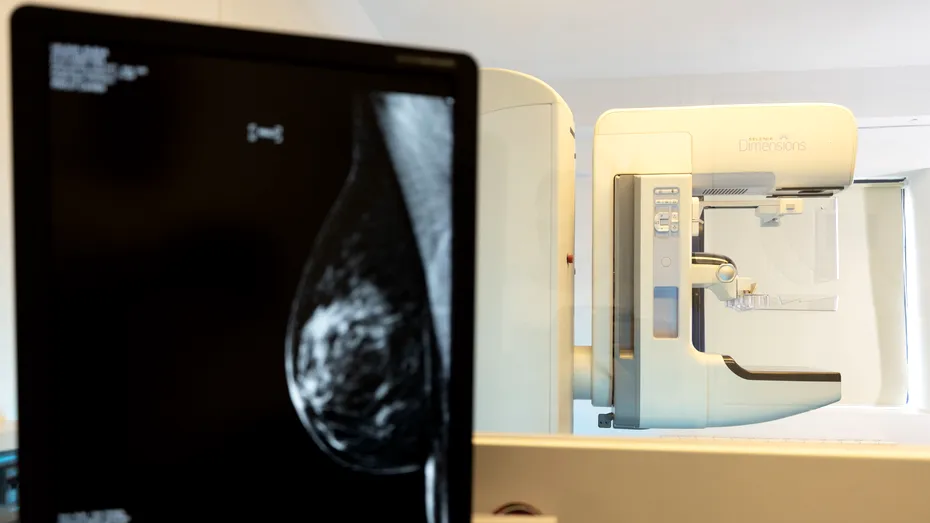

Ecografia de sân, care trebuie efectuată o dată pe an, este una dintre cele mai rapide metode atât de screening, cât și de diagnostic pentru afecțiunile mamare, inclusiv pentru cancerul mamar. De regulă, medicii recomandă ecografia mamară femeilor tinere, cu vârsta până în 40 de ani. Ulterior, femeile au indicație pentru mamografie, aceasta fiind, de altfel, și cea mai performantă investigație destinată screeningului și diagnosticului cancerului de sân. Chiar și în lipsa semnelor și simptomelor, mamografia permite identificarea chiar și a unor leziuni foarte mici, ce nu pot fi observate prin alte metode.

La SANADOR, pacientele au acces la consultații de specialitate, oferite de medici senologi foarte bine pregătiți și cu vastă experiență în diagnosticul și tratamentul cancerului de sân și la toate investigațiile necesare pentru stabilirea unui diagnostic corect. Femeile care aleg serviciile SANADOR beneficiază de ecografii mamare efectuate cu echipamente ultraperformante și de mamografii digitale 3D cu tomosinteză realizate cu unul dintre cele mai performante sisteme de mamografie – Selenia Dimensions 3D Hologic, care permite obținerea de rezultate superioare mamografiei digitale convenționale. De asemenea, examinarea prin rezonanță magnetică a sânului se realizează la SANADOR cu ajutorul unor echipamente RMN moderne, cu putere 3 Tesla. Spre deosebire de RMN convențional, echipamentele RMN 3 Tesla au o putere mai mare, astfel că furnizează imagini detaliate, într-un interval scurt.